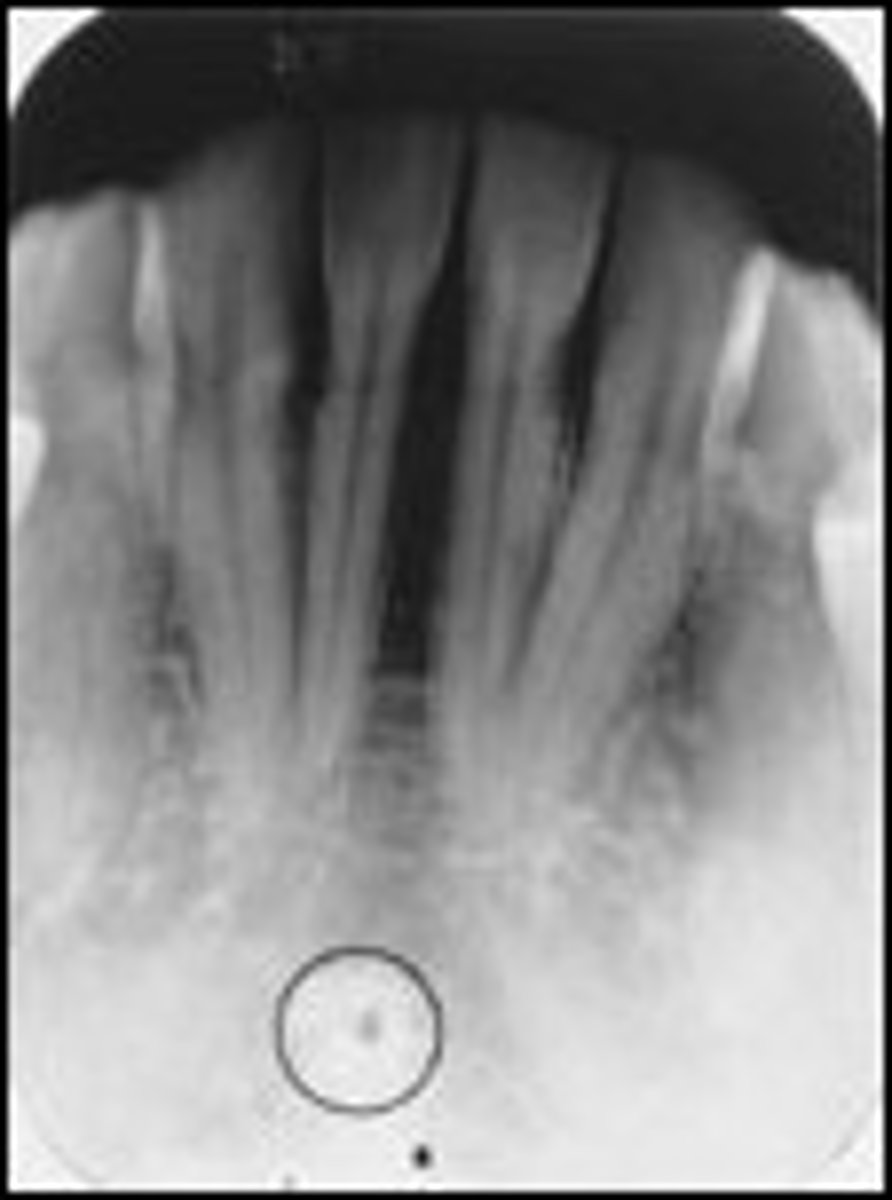

Incisive foramen

What is the radiolucent structure seen here?